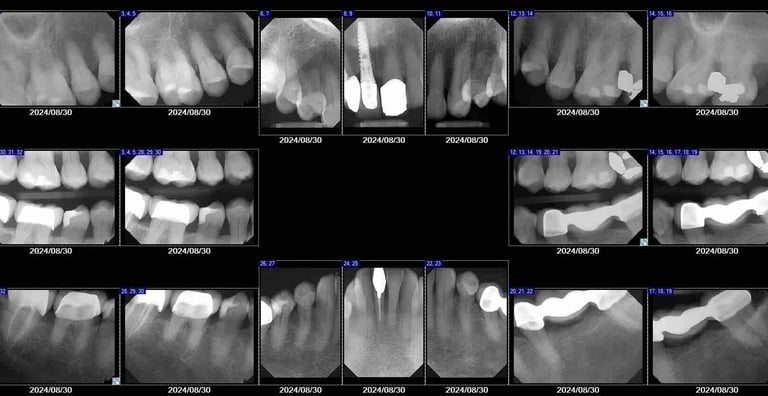

Digital dental X-rays use low-radiation technology to capture clear images of your teeth, roots, and jaw. They help detect issues that are not visible during a regular exam, such as cavities between teeth, infections, bone loss, and the position of unerupted teeth. Digital X-rays are fast, safe, and essential for accurate diagnosis.

Digital dental X-rays allow your dentist to see areas that are not visible during a regular exam. Depending on your needs, different types of X-rays may be used. Bitewing X-rays help detect cavities between teeth, while periapical X-rays show the entire tooth, including the root and surrounding bone. A full-mouth series (FMX) is often recommended for new patients to provide a complete overview of oral health. Panoramic X-rays capture the entire jaw, sinuses, and bone structure in a single image, and in more complex cases, a CBCT scan may be used to create detailed 3D images for implant planning or advanced treatment.